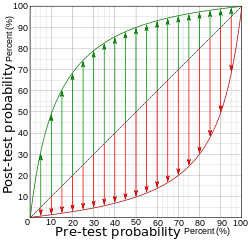

-

Diagram relating pre- and post-test probabilities, with the green curve (upper left half) representing a positive test, and the red curve (lower right half) representing a negative test, for the case of 90% sensitivity and 90% specificity, corresponding to a likelihood ratio positive of 9, and a likelihood ratio negative of 0.111. The length of the green arrows represent the change in absolute (rather than relative) probability given a positive test, and the red arrows represent the change in absolute probability given a negative test.

It can be seen from the length of the arrows that, at low pre-test probabilities, a positive test gives a greater change in absolute probability than a negative test (a property that is generally valid as long as the specificity isn't much higher than the sensitivity). Similarly, at high pre-test probabilities, a negative test gives a greater change in absolute probability than a positive test (a property that is generally valid as long as the sensitivity isn't much higher than the specificity). -